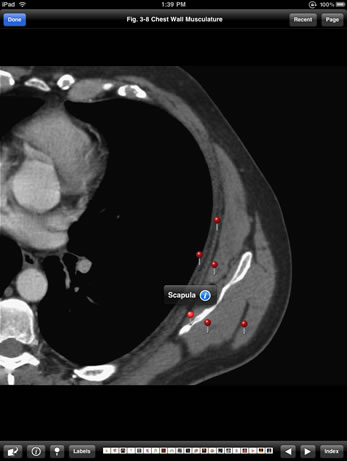

Match modern diagnostic images with a subset of the anatomic drawings from the Atlas of Human Anatomy, by Dr. Frank Netter, and enable a comfortable familiarity with how human anatomy is typically viewed in clinical practice.